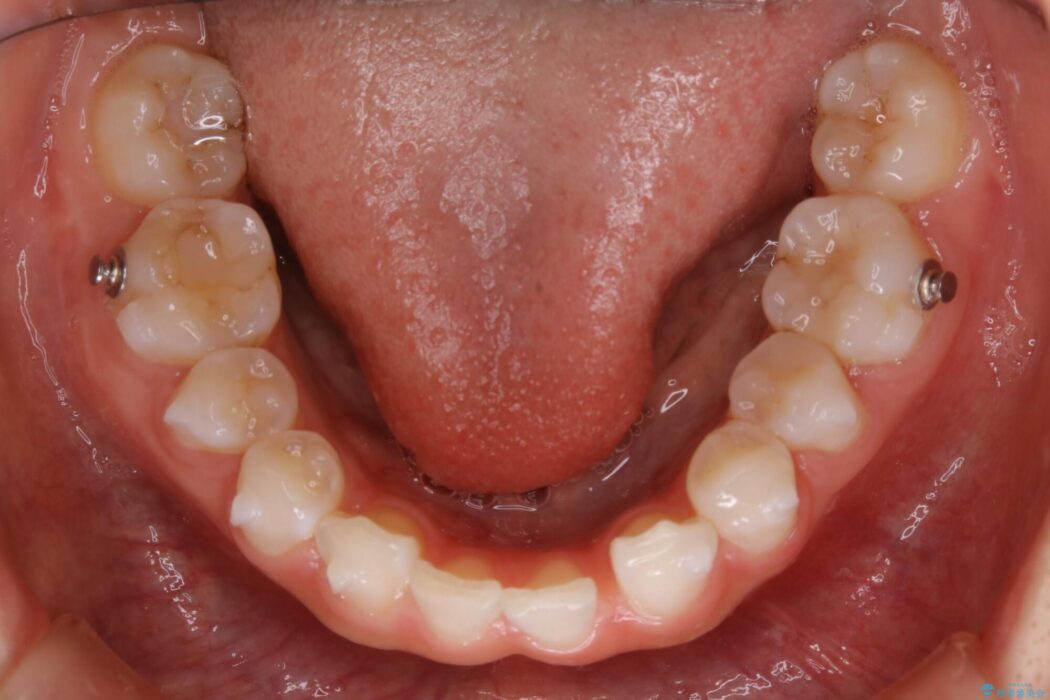

【20代女性】生まれつき歯の本数が足りない先天欠如を治療する

飛び出た八重歯による歯列のガタガタを主訴に来院されました。

診査したところ叢生だけでなく生まれつき永久歯の欠損、いわゆる先天欠如により歯の本数が少ないため噛み合わせなどにも影響が出ている状態でした。

特殊な状況からの矯正治療となるため、抜歯する本数や位置、歯列を整えるにあたって必要なスペースの確保を慎重に計画し、インビザライン コンプリヘンシブパッケージでのマウスピース矯正を行いました。